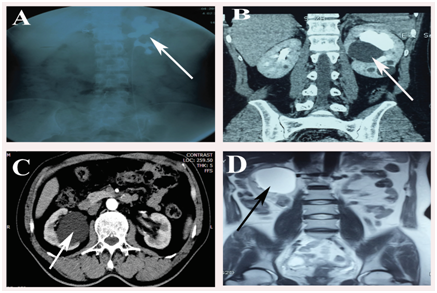

Patients who have parapelvic renal cysts are diagnosed either by ultrasound, computed tomography (CT) or IVU (intravenous urography) as shown in Figure 1. After confirmation of parapelvic renal cysts, and then urinalysis, urine culture, serum electrolytes, blood coagulation tests are evaluated prior to the treatment intervention. Patients with coagulopathy, cardiopulmonary insufficiencies or with active infections are excluded from undergoing this type of procedure. In all the studies, patients receiving transurethral marsupialization of parapelvic cysts were selected with strict selection criteria including; 1) Symptomatic patients such as flank pain, hypertension or hydronephrosis, 2) Patients with single parapelvic renal cyst compressing renal collecting system, 3) Patients with previous failed treatments 4) Patients without ureteral stricture, 5) Bosniak class I cysts on CT scan, 6) Cysts greater than 3cm and close to the pelvic wall.15,16 Some authors10,16 carried out ureteral stenting prior to the surgery about 1-2 weeks to passively dilate the ureter in order to attain smooth ureteral passage during the surgery, while other authors performed the procedure without prior stenting. According to Mahajan et al.,18 during RIRS (retrograde intrarenal surgery) reported that first setting flexible ureteroscope can reach to the kidney without prior ureter stenting, they have found that 94.5% success can be achieved when ureter access sheath is used. To prevent possible infections, prophylaxis antibiotics should be given to the patients before the surgery undertaken. Some investigators reported giving patients ceftriaxone (1.0g) 30 minutes prior to the surgery.16

Figure 1 A) Intravenous urography showing left kidney parapelvic cyst (Arrow pointing filling defect). B) and C) Examples of parapelvic cysts on computer tomography (CT) scan. D) Example of magnetic resonance image (MRI) showing parapelvic cyst of right kidney.